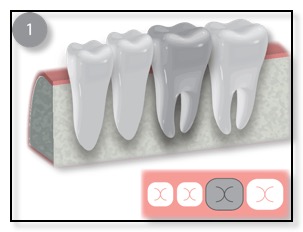

The other common type of bone graft for dental implants is a Ridge Augmentation, Ridge Enhancement, or Split Ridge. (See the diagram above.) Sometimes, when a patient has lost their tooth many months or years ago, the bone in that area has resorbed (the bone is lost). The remaining bone is too thin to support the dental implant. In such cases, Dr. Tsai would numb the area where the thin wall is, gently pull the gum tissue back, pack or place the bone graft in place, and suture the gum back into place. Sometimes Dr. Tsai will “split” the ridge and pack in the bone graft in order to thicken up the bone for the implant. This procedure typically takes 4-7 months to heal. Once the bone grafting has integrated or is healed, the dental implant can be placed.